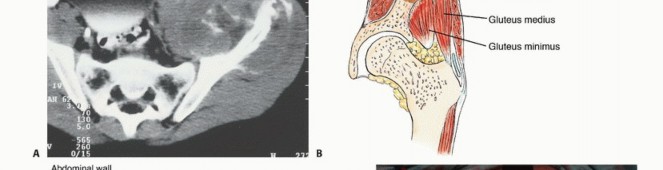

- التصوير المقطعي المحوسب (CT Scan): يوفر صورًا مقطعية مفصلة للعظام والأنسجة الرخوة، ويساعد في تحديد حجم الورم، مدى انتشاره داخل العظم، وعلاقته بالهياكل المحيطة.

- التصوير بالرنين المغناطيسي (MRI): يُعد الأداة الأكثر حساسية لتقييم الأنسجة الرخوة ونخاع العظم، ويكشف عن النقائل في مراحلها المبكرة، ويحدد مدى انتشار الورم في القناة الشوكية أو الأعصاب.